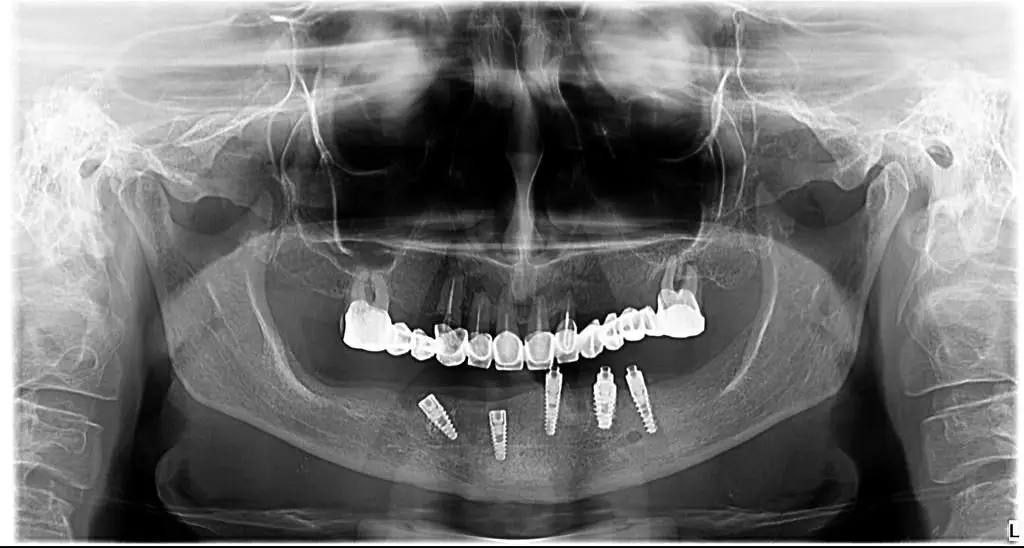

Consultul inițial – Am discutat despre dorințele pacientei și am făcut o evaluare completă a sănătății orale.

Am extras dintii irecuperabili, am practicat lifting de sinus maxilar (in unele situatii nu poate fi evitat) si am inserat 6 implanturi.